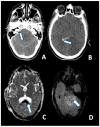

Figures